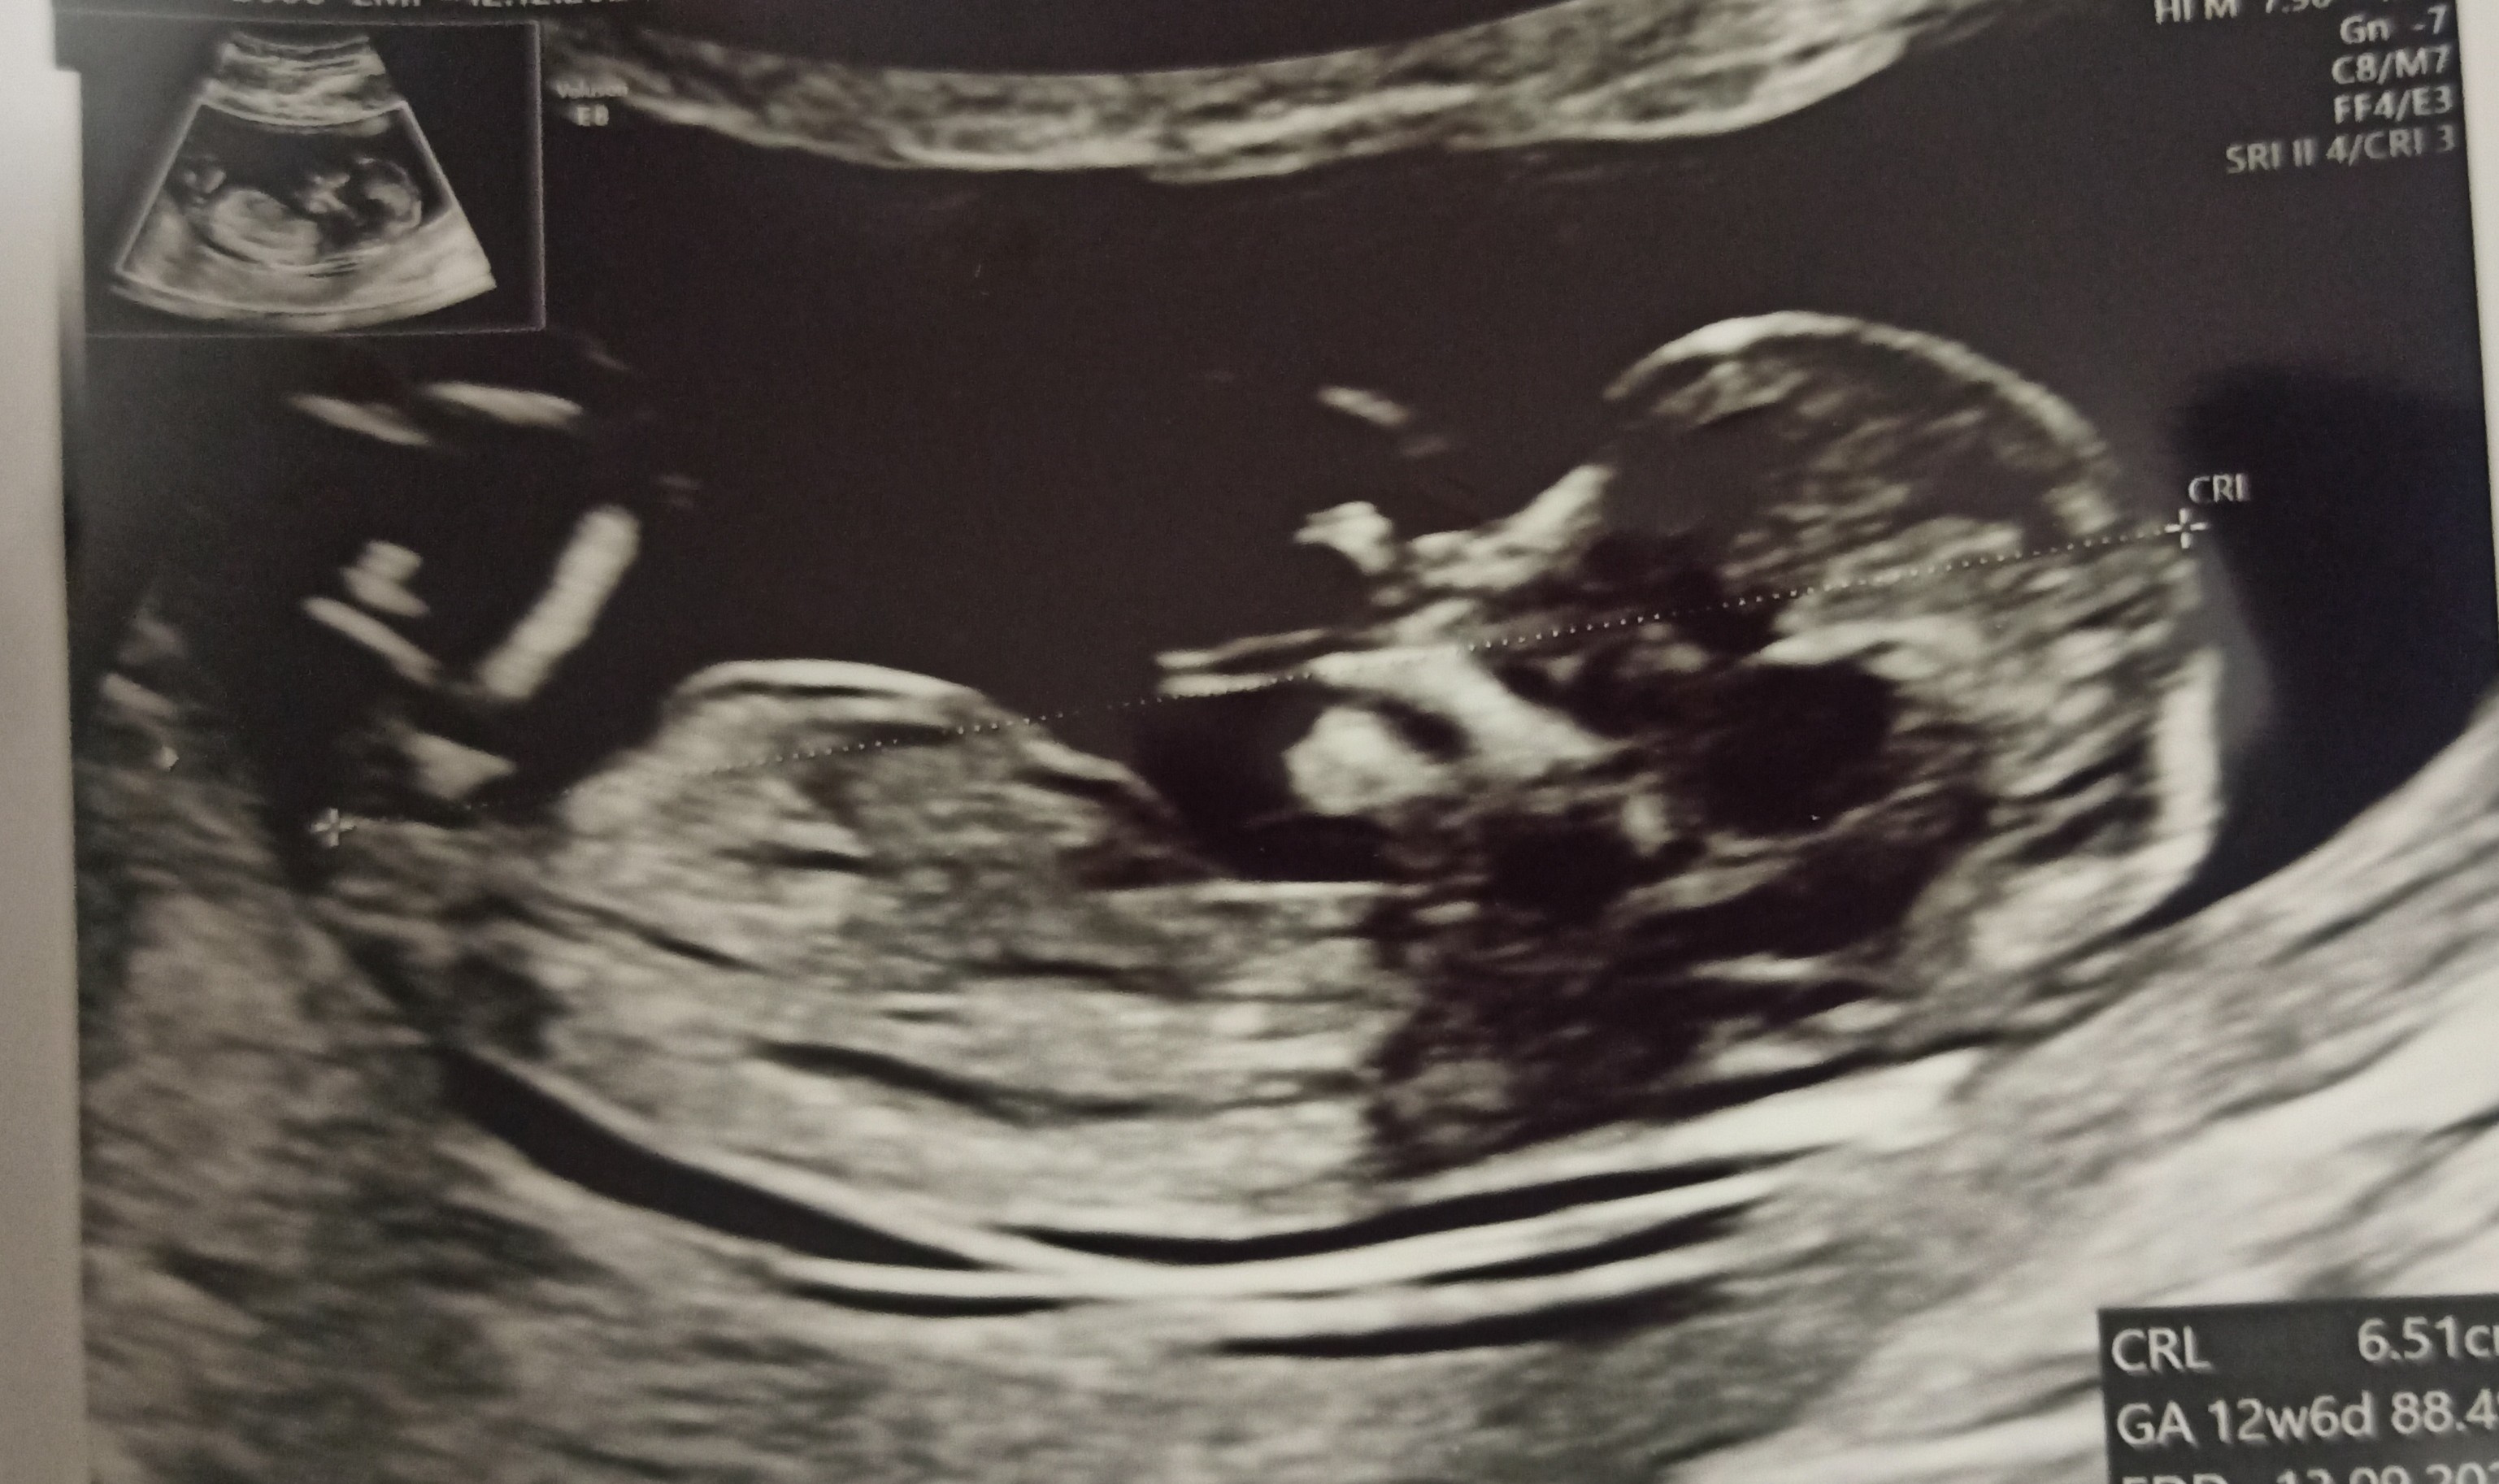

Dziewczyny, jestem po pierwszych prenatalnych (z pappa i plgf) i wszystko jest idealnie

tym razem doktorek nie zalecał badań genetycznych. Nie zdawałam sobie sprawy, jak bardzo byłam zablokowana obawami, że teraz coś będzie nie tak.

Lekarz mega pochwalił młodego (tak, "z dużą dozą prawdopodobieństwa" chłopiec teraz będzie

) za współpracę i mnie za super widoczność! Byłam w szoku, bo ja nie z tych chudych, raczej taka szczupła/ średnia.

Łożysko na tylnej ścianie macicy, więc super w kontekście mojego wcześniejszego cc.

Teraz można już wpisać nas z terminem porodu na 18.09.23